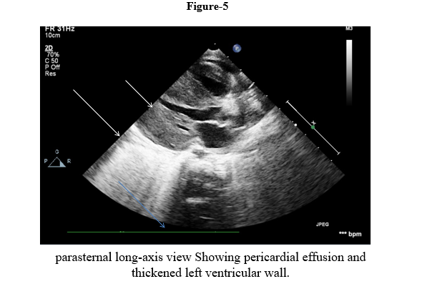

We report a four-month-old girl who presented in sudden cardiorespiratory collapse to illustrate an uncommon cardiac first sign of MTO1-related disease. The infant arrived hypotensive and obtunded with severe metabolic acidosis (pH 6.59; lactate 29 mmol/L). Chest radiograph showed cardiomegaly and bedside echocardiography revealed a large circumferential pericardial effusion producing compression of the right heart together with concentric left-ventricular hypertrophy. Emergency pericardiocentesis drained 120 mL of serous fluid and produced only transient improvement; over a prolonged PICU stay she had recurrent sterile effusions, four failed extubation attempts, refractory lactic acidosis, renal dysfunction and progressive bradycardia. Whole-exome sequencing identified a homozygous pathogenic MTO1 variant (NM_012123.4:c.1232C>T; p. Thr411Ile); both parents were heterozygous carriers. The family history included consanguinity and a sibling who died in early infancy after a similar illness. Despite maximal supportive care, she died on day 40 from cardiogenic shock and multiorgan failure. The case highlights that recurrent sterile pericardial effusion in an infant with hypertrophy and marked hyperlactatemia should prompt consideration of an underlying mitochondrial (MTO1-related) disorder and early genetic testing to guide counselling

The clinical phenotype of COXPD10 typically includes severe lactic acidosis, hypertrophic cardiomyopathy, developmental delay, and a generally poor prognosis, especially when presenting in infancy [2–4]. While hypertrophic cardiomyopathy is a well-recognized feature of this disorder, pericardial effusion with tamponade as the primary presenting symptom is exceedingly rare. This case aims to highlight this unusual cardiac manifestation of COXPD10 for cardiologists and intensivists, emphasizing the importance of considering mitochondrial disorders in the differential diagnosis of recurrent sterile effusions in infants.

This case illustrates tamponade as the initial cardiac manifestation of COXPD10. In infants, large effusions leading to tamponade should typically give rise to strong concerns for an infected, malignant, autoimmune, or post-surgical cause. Sterile recurrent effusions in addition to hypertrophic cardiomyopathy, in our patient, were suggestive of a metabolic cardiomyopathy.

Cardiomyopathy is a hallmark of COXPD10: O’Byrne et al. reported lactic acidosis in all 35 patients and cardiomyopathy in ~79% [2]. Zhou et al. described an infant with acidosis and early death [3], and Luo et al. reported another with compound heterozygous MTO1 variants and HCM [4]. Our case aligns with this phenotype but our case is distinctive in that it highlights pericardial tamponade as the critical event. The recurring effusions support a role of mitochondrial energetic failure in the development of capillary leak and edema. Within combined oxidative phosphorylation deficiencies, COXPD10 and COXPD23 (GTPBP3 mutations) in the audio-metabolic spectrum, both manifest with life-threatening HCM and acidosis age of onset of 1 year [8]. In contrast, COXPD1 (GFM1) and COXPD4 (TUFM) frequently present with hepatic failure and encephalopathy [9,10]; COXPD7 (C12orf65) has a later onset and symptomatology of neuro-ophthalmologic disease and uncommon cardiac disease [8]. So, in the setting of HCM and a sterile effusion, mitochondrial translation defects, in particular MTO1 and GTPBP3, should be considered by the cardiologist. Pericardiocentesis is life-saving for tamponade, but does not address the etiology, and recurrences occur in over 50%. The so-called mitochondrial contraceptive "cocktail" is widely utilized, though without evidence of aneuropathy efficacy in COXPD10 [2,4]. Dichloroacetate may also decrease lactate temporarily, but does not affect outcome [2,12]. Current approaches therefore do not alter disease course, and aggressive supportive care and counseling are issues of central management.